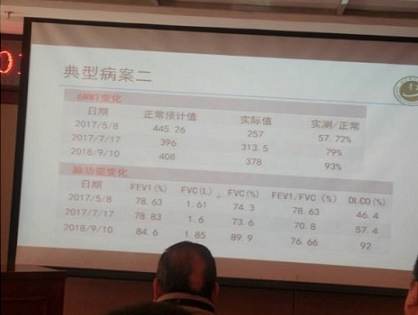

특발성폐섬유증과 같은 간질성폐질환은 예후가 좋지 못하다고 알려진 병입니다. 하지만 한약 치료를 통해 이 병을 극복하려는 노력이 진행되고 있습니다.